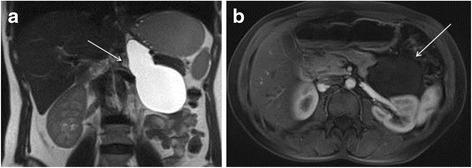

We report here the case of a 38-year-old woman who was diagnosed with a cystic retroperitoneal mass. After further investigations, the patient was suspected to have a left adrenal cystic lymphangioma. She underwent successful open left adrenalectomy as curative treatment, and the diagnosis of cystic lymphangioma of the left adrenal gland was confirmed at histology. The postoperative course was uneventful.

我们在此报告一例38岁女性,她被诊断为腹膜后囊性肿块。经过进一步检查,怀疑该患者患有左肾上腺囊性淋巴管瘤。她接受了成功的开放性左肾上腺切除术作为根治性治疗,组织学检查证实为左肾上腺囊性淋巴管瘤。术后过程顺利。